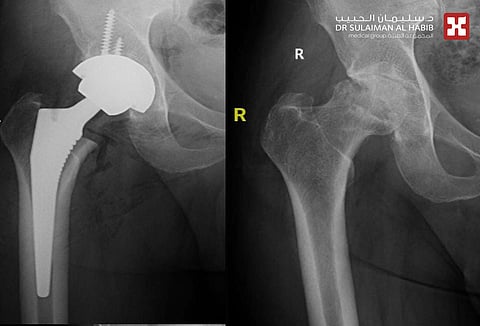

والذي أضاف أن المريض وصل للعيادة مستعينًا بعكازين؛ حيث تم الاستماع إلى شكواه، وعمل الفحص السريري، تبعه إجراء حزمة من التحاليل المخبرية والفحوصات بالأشعة السينية الرقمية "Digital x-ray". وقد أبانت النتائج بدقة وجودَ خشونة شديدة من الدرجة الرابعة وتنخر في رأس مفصل الورك، بالإضافة إلى حدوث تيبُّس وهبوط في المفصل مسببًا قصر طول في الساقين وعدم الاتزان أثناء المشي.

مفيدًا بأن العملية استغرقت ساعة وأربعين دقيقة، وتم فيها عمل فتح جراحي بسيط في منطقة الورك الخلفية وفق التكنيك الحديث، ومن ثم معالجة قصر الطول واستبدال مفصل الورك بآخر جديد يتميّز بالجودة العالية والعمر الطويل من الاستخدام، مصنوع رأسه من مادة السيراميك المطور وجذر معدني.